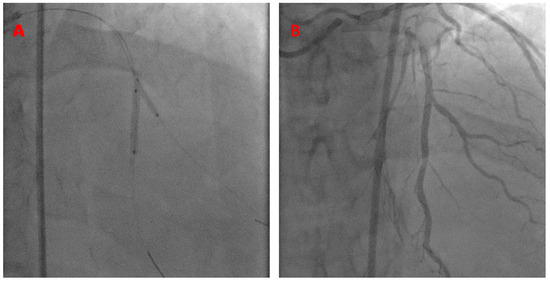

- Case # 2